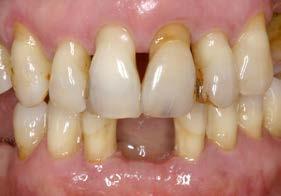

Figuras 2-3. Imágenes intraorales que evidencian pérdida ósea generalizada, extrusión de dientes anteriores y recesiones en todas las piezas presentes.

Se presenta el caso de una mujer de 65 años con diagnóstico de periodontitis severa al inicio del tratamiento. El examen clínico evidenció pérdida

Figura 1. Radiografía panorámica inicial que muestra la enfermedad periodontal avanzada de la paciente, con ausencia de varias piezas dentales y otras de mal pronóstico.

Implantes y propiocepción: la importancia de preservar dientes clave en pacientes con enfermedad periodontal avanzada

ósea vertical generalizada, defectos angulares en sectores posteriores y múltiples ausencias dentarias en ambos maxilares. La inspección intraoral mostró recesiones gingivales, exposición radicular y colapso del tercio anterior como consecuencia de migración dentaria y pérdida de soporte (Figura 1-3).

En la fase inicial del tratamiento se priorizó un enfoque conservador. Se realizaron las exodoncias de las piezas con pronóstico irrecuperable y se procedió a la preservación de los alvéolos mediante PRGF-Endoret, según la técnica descrita por Anitua et al.18 Los dientes remanentes fueron ferulizados temporalmente para servir como provisionales, favoreciendo la estabilidad hasta la colocación de los implantes tras la cicatrización (Figura 4 y 5).